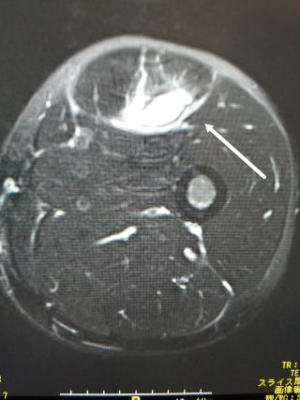

上から6週間目、初診時、初診直後のMRI

症状が出てから日が浅いとレントゲンには何の所見もありません。(写真左)臨床所見として同部に圧痛を認めるのみです。

日にちが2-3週間経過すると仮骨を形成し骨皮質の肥厚を認めます。(写真中央)

MRIは症状出たときから画像に変化があるので、早急に鑑別診断を行う場合にはとても有効です。(写真右)

骨粗しょう症など骨の脆弱性によって荷重部分である骨頭が病的骨折を起こす。高齢者や骨粗しょう症がある場合に、たくさん歩いたり転倒しそうになるなど微少な外傷を起点として大腿骨頭軟骨下の脆弱性骨折が起こるとされる。はっきりとした誘因が無い場合もある。急激な歩行時の股関節部の痛みが生じることが多い。

検査はレントゲンでは初期には変化が無く、精査としてMRIをを行う。鑑別診断としては、特発性大腿骨頭壊死、一過性大腿骨頭萎縮症がある。骨頭が保たれていれば局所の安静、免荷を行う。痛みには消炎鎮痛剤を使用する。骨頭が圧潰するようなら人工骨頭置換術となる。股関節唇損傷を高頻度に合併している。難治性のSIFFHに関節鏡にて関節唇を修復する手術を行い治療する方法が近年、報告されている。